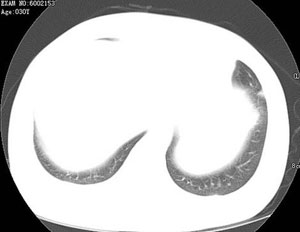

女性,30岁。

病史为胸痛20多天,无畏寒发热,无消瘦,无咳嗽咳痰。总之症状很逍遥。

临床以胸痛待查收住入院。

双肺野可见散在大小不等结节及肿块影,内密度不均匀,边缘部分清,部分欠清,纵隔未见明显肿大淋巴结.右侧胸腔少理积液.结合临床,考虑韦格肉芽肿可能吧,巨淋巴增生,结节病,特殊感染都要考虑.转移瘤临床不象.

两肺散在分布大小不等的肿块及结节影,边缘毛糙,有分叶、毛刺,病灶密度不均匀,可见支气管充气相与空泡征。病变大多位于胸膜下,可见胸膜凹陷及胸腔积液。气管腔静脉间可见小结节影。

考虑肺真霉菌病;心脏增大,肺动脉增宽